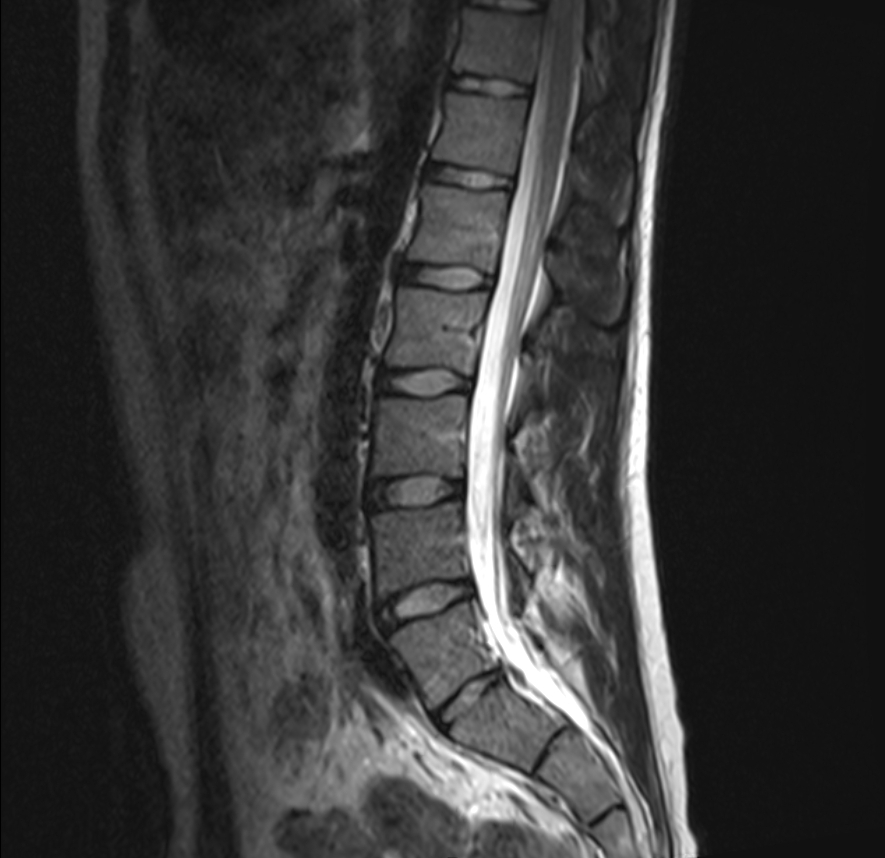

In der modernen Radiologie spielt die Zweitbefundung eine entscheidende Rolle, um die bestmögliche Diagnosesicherheit zu gewährleisten. Sie bietet Patienten und Ärzten eine zusätzliche Ebene der Absicherung, indem sie eine unabhängige Überprüfung der bereits gestellten Diagnose durch einen zweiten Radiologen ermöglicht. Diese Praxis kann besonders wertvoll sein, wenn es um komplexe oder seltene Krankheitsbilder geht, bei denen eine präzise und genaue Diagnose unerlässlich ist.

Mein Ziel ist es, Ihnen größtmögliche Sicherheit und Klarheit zu bieten, indem ich meine Expertise einsetze, um eventuelle diagnostische Unsicherheiten auszuräumen. Kontaktieren Sie mich gerne, um mehr über Zweitbefundungen zu erfahren.